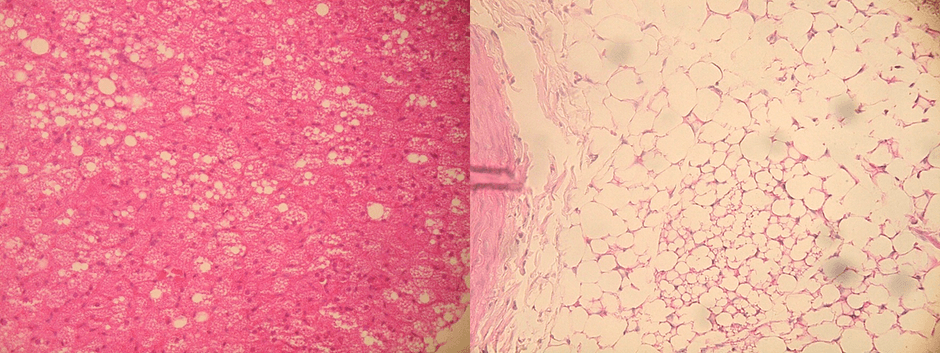

この原因を明らかにするために、腹部と胸部それぞれの血管周囲脂肪組織の詳細な解析を行ったところ、高脂肪食と高シュークロース食で影響を及ぼしやすい脂肪細胞の種類が異なることが示されました。高脂肪食は主に白色脂肪細胞に影響を与え、高シュークロース食は主に褐色脂肪細胞に影響を与えることが分かり、主に白色脂肪細胞で構成される腹部の血管周囲脂肪組織は、高脂肪食摂取の影響を受けやすく、褐色脂肪細胞が多く存在する胸部の血管周囲脂肪組織は、高シュークロース食摂取の影響を受けやすいことが示唆されました。

※2 白色脂肪細胞:見た目が白色に近いことから白色脂肪細胞と呼ばれる。中性脂肪を貯める機能を持つ細胞で、アディポサイトカインと呼ばれる生理活性物質を分泌する。アディポサイトカインは生命活動に重要な役割を持つ一方で、アディポサイトカインの分泌異常は、動脈硬化や糖尿病など様々な疾患に関与することが報告されている。お腹周りの脂肪は主に白色脂肪細胞で構成される。腹部の血管周囲脂肪組織を構成する脂肪細胞のほぼすべてが白色脂肪細胞である。

※3 褐色脂肪細胞:見た目が褐色に近いことから褐色脂肪細胞と呼ばれる。中性脂肪を燃焼して熱を作りだす細胞。胸部の血管周囲脂肪組織には褐色脂肪細胞が多く、白色脂肪細胞も一部存在する。